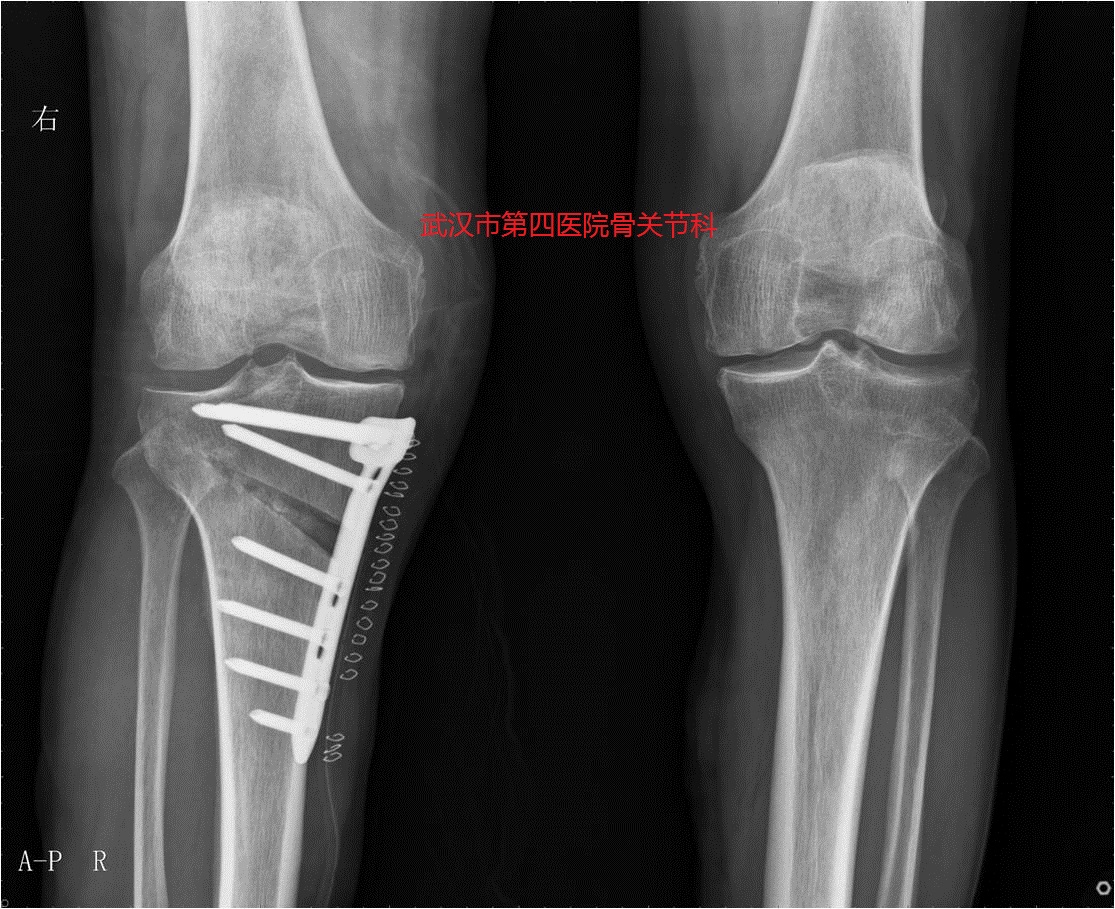

2.保膝手术-截骨手术:如果膝关节骨关节炎合并有关节外畸形,可以考虑行截骨矫正畸形,细分为股骨侧、胫骨侧的畸形矫正。

保膝手术:股骨远端截骨术

保膝手术:胫骨近端截骨术